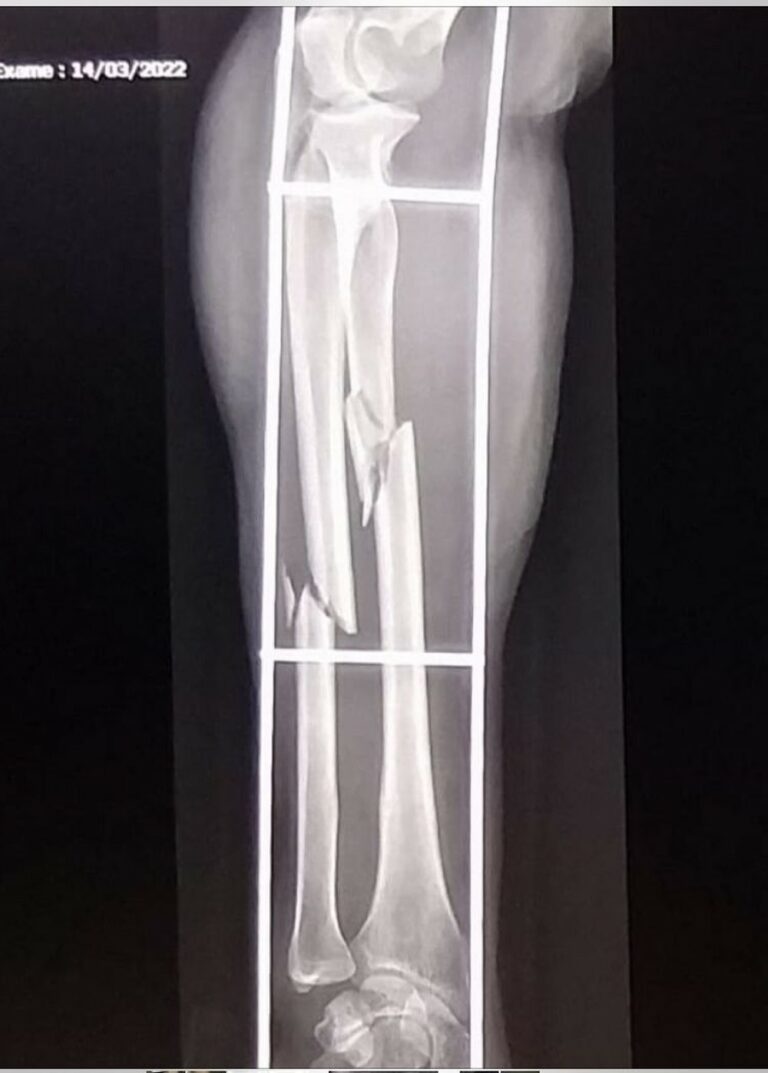

Um homem, de 39 anos, foi preso em flagrante após ter invadido a casa e espancado uma indígena e seu marido. A mulher fraturou o antebraço e precisou ser transferida para Três Lagoas, a 326 km de Campo Grande, onde deve passar por cirurgia.

Ele foi detido e encaminhado à Delegacia de Polícia, onde foi reconhecido por uma das vítimas. A mulher indígena foi medicada no município e transferida para Três Lagoas, onde deverá passar por cirurgia.